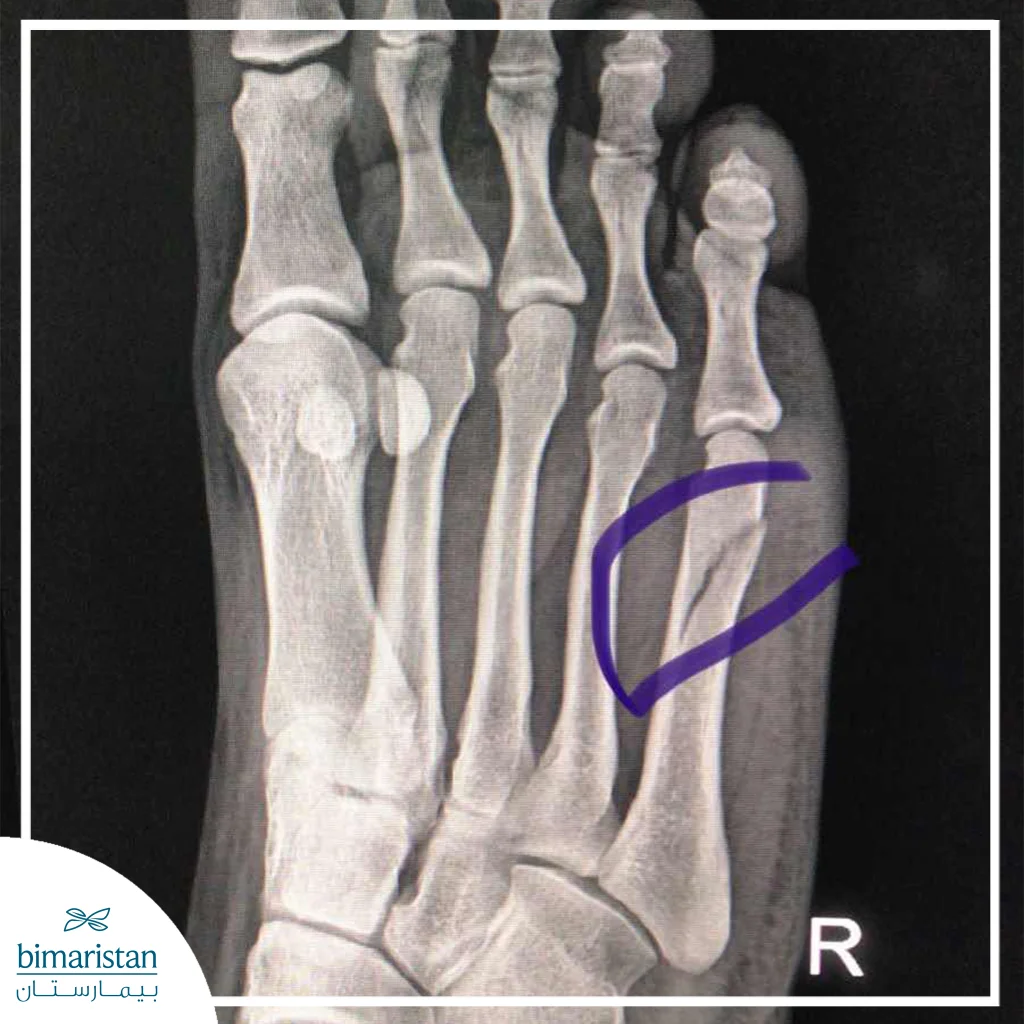

الأشعة السينية

تُستخدم للكشف عن معظم الكسور العادية وغير المعقدة، تظهر صورة العظام بشكل واضح وتحدد موقع الكسر وتحرك طرفي العظمة، الفحص السريري يدعم الصورة الشعاعية عبر تحديد مناطق الألم والكدمات والتورم.